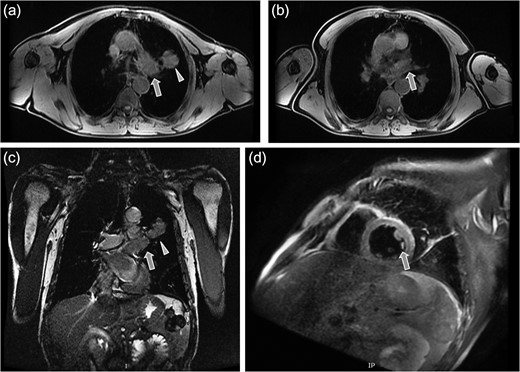

A 61-year-old male, with a history of heavy tobacco abuse presented with dyspnea, left thoracic pain and productive cough. He did not report palpitations or hemoptysis. Chest radiography showed an abnormal shadow in the left upper lung field. Computed tomography (CT) scan revealed a solid lesion of the left upper lobe, 2.9 × 1.8 cm2 in size, with irregular borders (Fig. 1a and c). The tumor seemed to infiltrate the upper left pulmonary vein which appeared dilated and totally occluded due to the presence of thrombotic material in its lumen (Fig. 1b and d). Transthoracic echocardiography showed an intracardiac structure, 4 × 2.5 cm2 in size, protruding from the left pulmonary vein, having no adhesions to the atrial walls. Magnetic resonance imaging (MRI) confirmed the above findings. (Fig 2a–d). A positron emission tomography scan (PET) was also performed. It confirmed the CT findings showing an irregular nodular lesion in the left upper lobe with irregular margins and a diameter of 2.8 cm. It showed a hypermetabolic activity (SUVmax = 29.6) (Fig. 3a and c). It also showed a pleural lesion ventrally to the upper lobe parenchyma. Another hypermetabolic focus (SUVmax = 21.4) appeared in the lumen of the upper lobe pulmonary vein (Fig. 3b and c). Bronchoscopy showed the presence of abnormal tissue in the apicoposterior segmental bronchus of the left upper lobe. Tissue biopsies were obtained but showed no signs of malignancy. Spirometry revealed a mild obstructive pattern. A complete staging work-up, including head CT scan, abdominal ultrasound and whole body bone scintigraphy, did not show any distant metastasis. Based on these the preoperative staging was T4N0M0. Despite failure to obtain a pathologic diagnosis, a surgical treatment including left pneumonectomy with entry in the left atrium and removal of the intracardiac thrombus under cardiopulmonary bypass (CPB) was decided based on the potential immediate life-threatening situation. The presence of such an intracardiac thrombus could be associated with secondary migration, acute blockage of the mitral valve and heart failure, or a distal arterial embolisation resulting into a fatal stroke, a mesenteric ischemia or a severe peripheral ischemia [2, 4]. Median sternotomy was the surgical approach and the patient was cannulated using bicaval venous return and underwent CPB. Left pneumonectomy was carried out, initially with left pulmonary artery ligation and resection, followed by resection of the left pulmonary veins and part of the wall of the left atrium together with the intraatrial mass, which was removed en bloc. The left atrium was sutured closed and then the left main bronchus was resected, completing the left pneumonectomy. The nodal stations 4, 5, 7, 8 and 9 were also sampled. The surgical specimen (Fig. 4) showed the same features as those seen on the CT scan. The patient was successfully extubated directly after the operation and was transferred to the ward on the first postoperative day. The patient was discharged on the 12th postoperative day and received adjuvant chemotherapy thereafter.

Magnetic resonance tomography images which confirmed the CT findings. (a) Axial plane showing the irregular solid mass in the left upper lobe (triangular pointer). (b and c) Axial and coronal plane showing the dilation and occlusion of the left upper pulmonary vein (arrow). (d) Sagital reconstruction revealing the dilation of the left upper pulmonary vein and the presence of thrombotic material in its lumen (arrow).